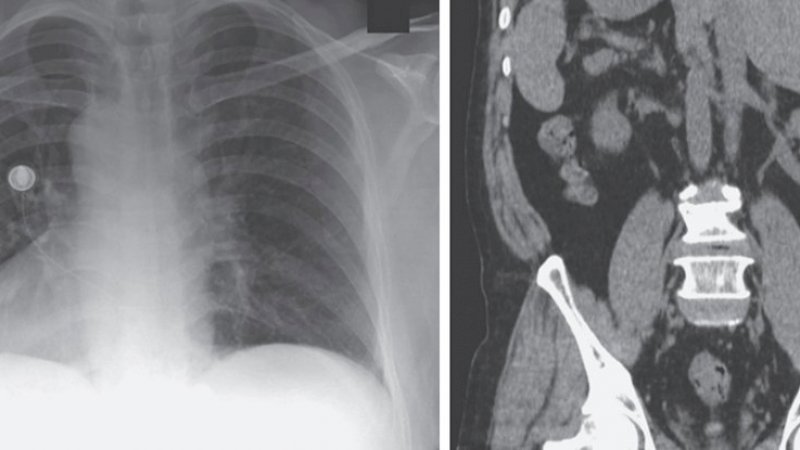

Dokternya menyebutkan bahwa pasien baru saja berimigrasi ke AS setelah tinggal di kamp pengungsi selama 20 tahun. Di antara temuan aneh yang ditunjukkan oleh rontgen dada adalah dextrocardia (di mana puncak jantung ada di kanan, bukan di kiri) dan "transposisi gambar cermin" pada organ perut.

Gejala pria itu termasuk nyeri dada, batuk, dan rasa sakit di sisi kiri perut, menurut laporan medis. Untungnya, itu ternyata hanya infeksi saluran pernapasan atas; setelah dirawat karena sakit dengan obat antiinflamasi, pasien sembuh beberapa hari kemudian.